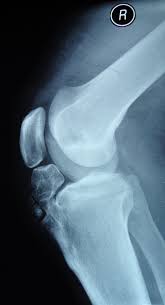

Diagnosis is made clinically with an enlarged tibial tubercle and supplemented with radiographs of the knee that reveal irregularity and fragmentation of the tibial tubercle. Osgood-Schlatter disease is an overuse injury of the knee common in growing adolescents. Osgood-Schlatter is a common disease with most cases resolving spontaneously with skeletal maturity.

Osgood Schlatter Disease Collection Of Plain X Rays